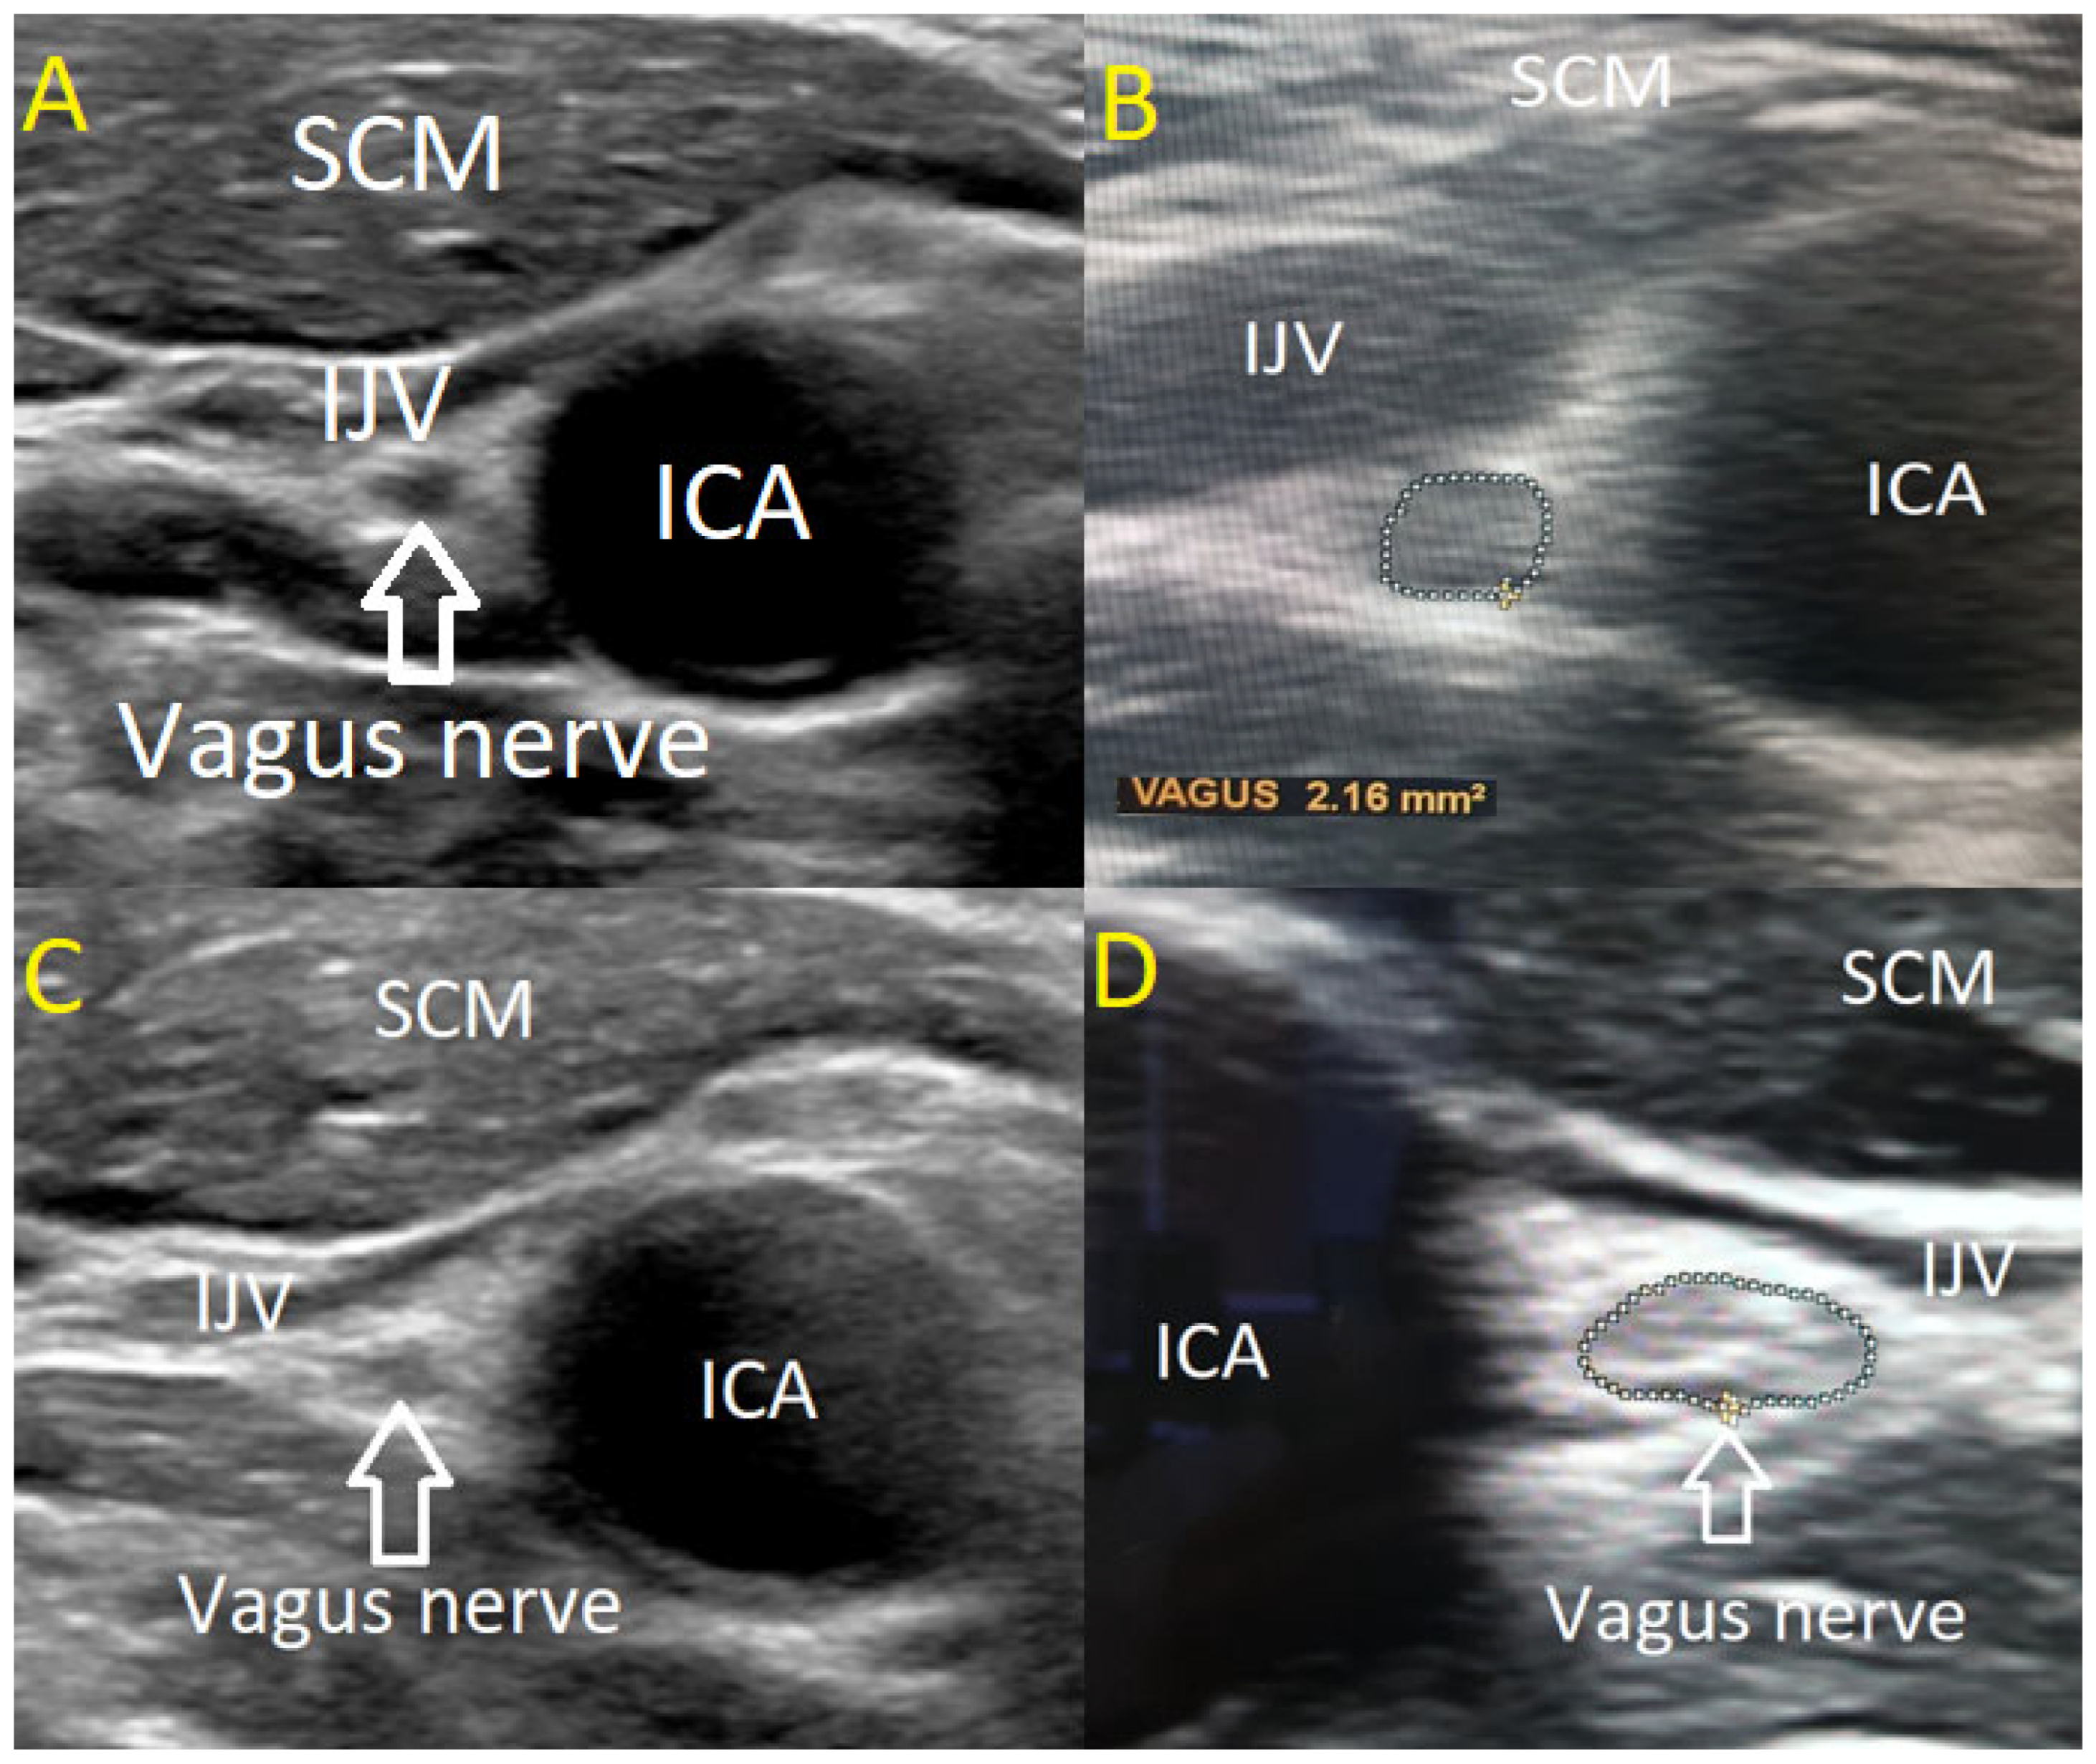

The USVN was performed by two investigators using a high-resolution Philips EPIQ 7 ultrasound system equipped with a linear 4–18 MHz transducer (CE 0086). The transducer was positioned transversely above the clavicle in the cervical region, aligning with the level of the levator scapulae muscle where the VN courses along the anterior scalene muscle. In B-mode ultrasonography, the VN was visualized adjacent to the carotid artery bifurcation, posterior to the confluence of the internal and common carotid arteries. The nerve was identified within its connective tissue sheath, exhibiting a characteristic sonographic appearance with a centrally hypoechoic region surrounded by a hyperechoic periphery.

VN diameter was measured in millimetres using cross-sectional imaging at two predefined locations: near the carotid bulb and at the junction where the common carotid artery bifurcates. Both quantitative and qualitative characteristics of the nerve were evaluated, including its structural homogeneity (classified as homogeneous or heterogeneous) and echogenicity (categorized as hypoechoic, isoechoic, or hyperechoic).

The CSA of the VN was determined in a transverse plane by tracing the hypoechoic nerve region within the hyperechoic border, following the methodology established by Walter et al. in 2018 [19]. Measurements were obtained independently by two examiners, each assessing one side three times with a precision margin of 0.01 mm2. The mean of the three measurements was calculated for each side, followed by a grand average across both sides. To ensure measurement reliability, both examiners were blinded to each other’s results. The measuring methodology and VN anatomical structure are illustrated in Figure 1.

Figure 1. (A) Normal results of the USVN in a healthy volunteer (hypoechoic, homogenic). (B) Methodology for measuring CSA of the VN by ultrasound (isoechoic, homogenic). (C) USVN of ALS patient (hyperechoic, homogenic). (D). USVN of ALS patient (hyperechoic, heterogeneous). SCM—sternocleidomastoid muscle. IJV—internal jugular vein. ICA—internal carotid artery.